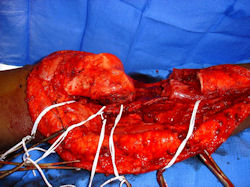

Examples of radical limb sparing surgeries for osteosarcomas in various anatomic locations (distal femur, proximal tibia, proximal humerus, scapula)

In each case, the tumor and bone from which it arose were resected. This required meticulous dissection, mobilization and preservation of adjacent pertinent neurovascular structures. In each case presented here, the defect was reconstructed with a special modular segmental tumor prosthesis. This also replaces the adjacent joint in many instances.

Limb-sparing surgery for osteosarcoma of distal femur – Intraoperative photos